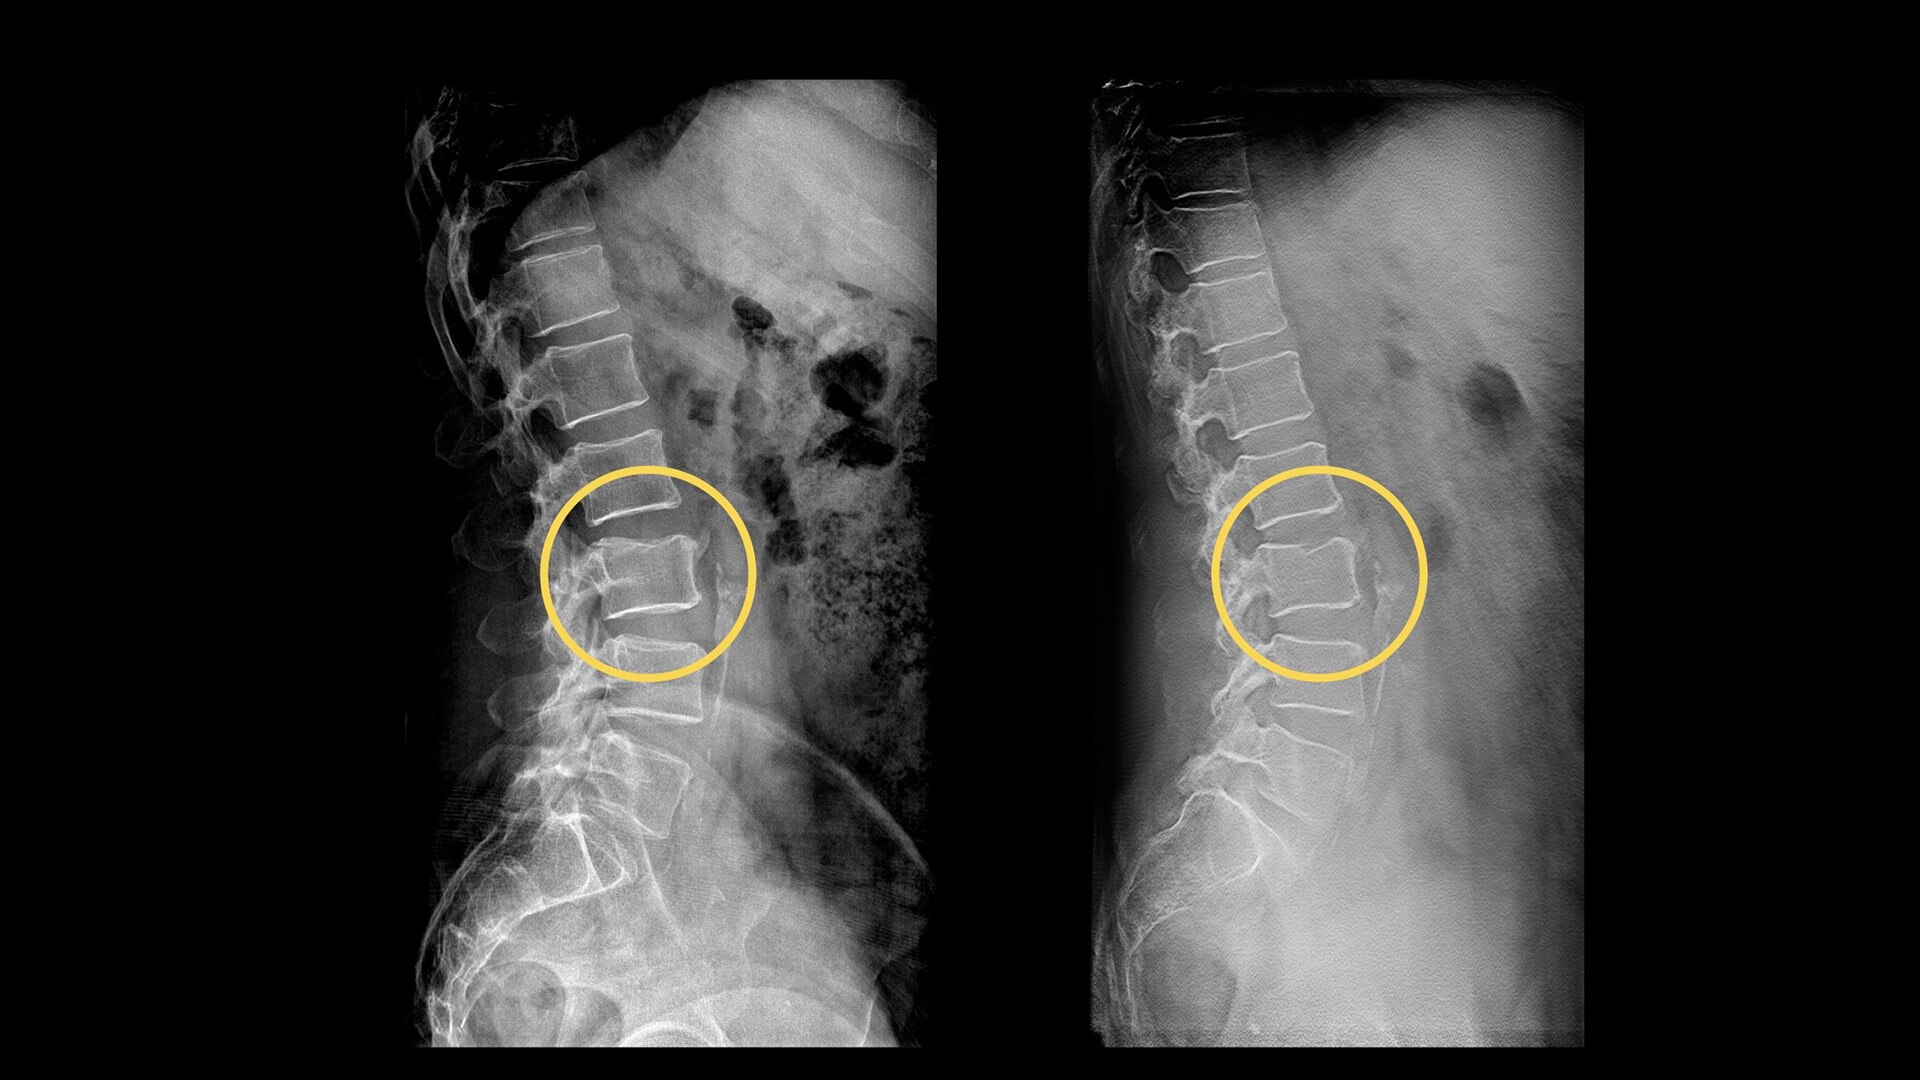

Your department relies on standard radiography as the first diagnostic test for most chest, orthopedic and trauma cases. But hairline fractures or non-displaced fractures are difficult to detect on conventional X-rays.13 According to a recent study, 33% of scaphoid fractures are missed on the first X-ray.14

13. P. M. Parizel et al. "Trauma of the spine and spinal cord: Imaging strategies." Eur Spine J. 2010 Mar; 19(Suppl 1): 8–17.